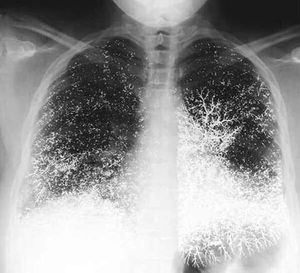

A strange view of the accumulation of mercury in pulmonary blood vessels.

Cxr

Mercury

Plumonary